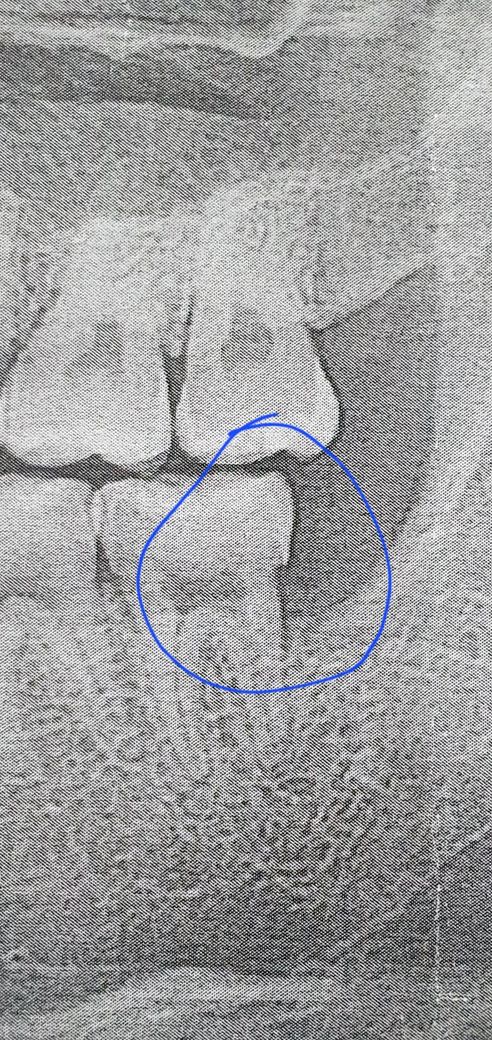

매복 사랑니 발치 미루다가 뽑았는데 앞 어금니 옆면이 사진처럼 각지고 부자연스럽게 패였습니다

• 1번 째 사진

• 사랑니가 있었을 때 해당 부위에 음식물이 끼게 되었다면 해당 부위가 충치를 발생시키면서 사진과 같은 모양이 될 수 있습니다이 정도는 크게 문제를 발생시키지 않지만 걱정이 되신다면 해당 부위를 치료해 볼 수 있습니다 자세한 확인을 위해서 치과에서 진료를 받아 보는 것을 권유 드립니다

• 발치 전 후 사진이 있다면 좀 더 판단에 도움이 되겠습니다 만약 사랑니가 영향을 주어 해당 치아가 저렇게 원래 파여있게 된 것일 수도 있겠으나 사진상으로만 저렇게 보이는 것일 수도 있습니다 cervical burn out 이라고 합니다